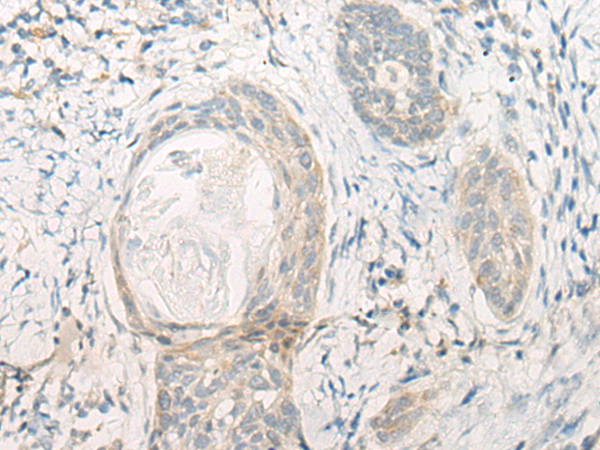

The image is immunohistochemistry of paraffin-embedded Human thyroid cancer tissue using 47045(DENND1B Antibody) at dilution 1/20. (Original magnification: ?00)

The image is immunohistochemistry of paraffin-embedded Human esophagus cancer tissue using 47045(DENND1B Antibody) at dilution 1/20. (Original magnification: ?00)